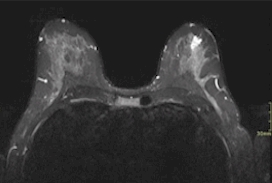

2023 London Imaging Discovery Day